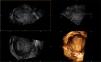

ObjectivePrimarily to assess the agreement between three-dimensional transvaginal (3D TVUS) and saline-infused sonohysterography (SIS) for the diagnosis and evaluation of the parameters of CSD. The secondary objective was to evaluate patients’ satisfaction and tolerability with each procedure, in addition to the cost.

Results3D TVUS and SIS showed nearly good agreement regarding the detection of CSD with a kappa (κ) of 0.780 (p<0.001). Regarding the assessment of the parameters, no significant differences were observed between the two modalities regarding depth, length, and width of CSD (p>0.05), but there was a significant difference in the assessment of the volume (p=0.004). 3D TVUS was considerably more expensive (300.00±0.00 LE) than SIS (231.11±31.65 LE, p<0.001), but it took less time (5.94±0.79min vs. 14.85±1.32min, p<0.001). With 3D TVUS, all patients (100%) expressed high levels of tolerability and satisfaction, but with SIS, tolerability and satisfaction were 8.3% and 90.3% (p<0.001 and p=0.007, respectively).

ConclusionThe comparison between 3D-TVUS and SIS in evaluating cesarean scar defects (CSD) demonstrated a high level of agreement. Moreover, the findings highlight the advantages of 3D-TVUS over SIS in terms of ease of use and patient preference, offering greater satisfaction, better tolerance, and improved time efficiency.